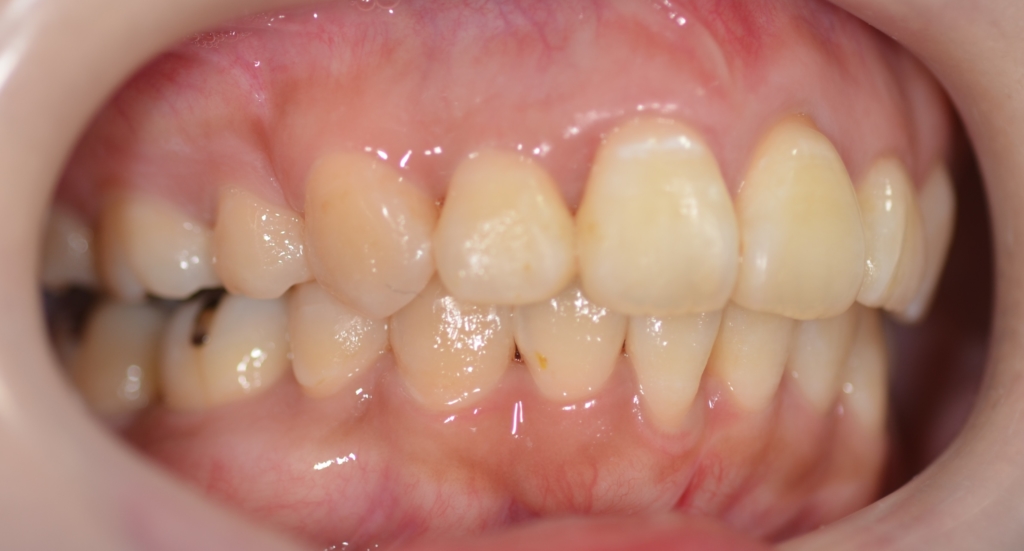

次は、歯並びや横顔・口元の比較です。

左側が矯正治療前、右側が矯正治療後

上段が矯正治療前、下段が矯正治療後